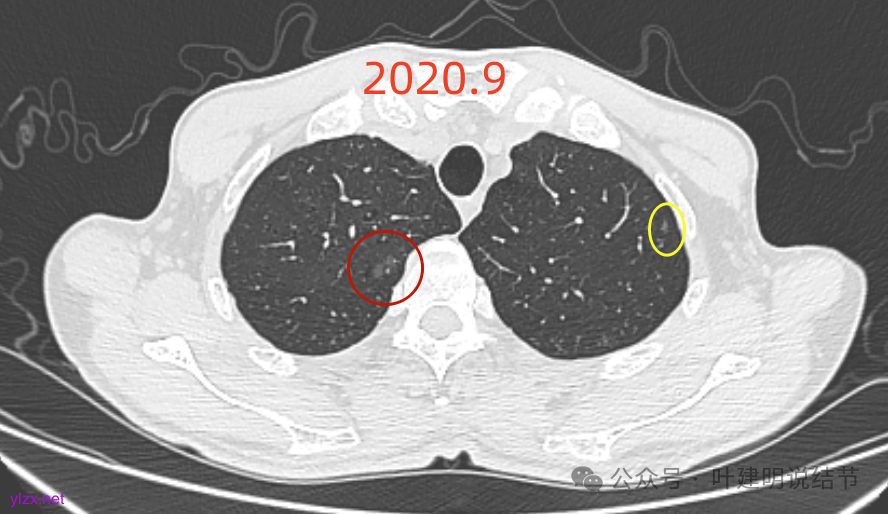

先看2020年9月的片子:

右上叶近脊柱旁有淡而纯的磨玻璃结节,整体轮廓与边界清楚,没有明显实性成分,也未见确切胸膜牵拉凹陷。

左上胸膜下有处偏长条小结节,也是磨玻璃密度的,轮廓较清。

左上叶混合密度结节,有毛刺与空泡征,瘤肺边界稍糊,灶内密度较为杂乱不均。